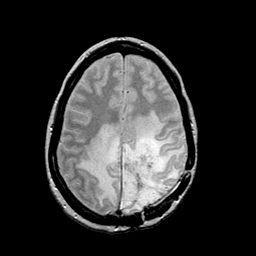

MR Study #2 -- Slice #37

Tour 2: Next/Previous/Start: This tour will examine the cerebral edema which corresponds generally to the high signal extending from the center of the mass through surrounding white matter. On this proton-density-weighted image, the high signal corresponding to edema respects the gray-white junction, but tends to spare the "u"-fibers. This is a common observation in the white matter reaction to malignant neoplasia, so-called "vasogenic" edema. Choose a spatial movie (by clicking "cine" next to the sagittal image) of the proton density stack to see the extent of the edema.